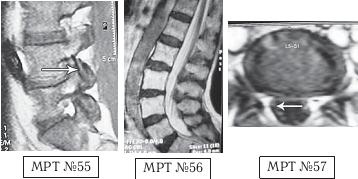

На МРТ № 54 наблюдается изменение физиологического лордоза, стеноз спинномозгового канала, грыжа межпозвонкового диска и спондилёз в сегменте LIII-LIV, ретроспондилолистез — LIV и LV. Как правило, причина вышеупомянутых болей при таких патологиях скрывается в дугоотростчатых суставах. Дело в том, что при изменении физиологического лордоза извращается «работа» и дугоотростчатых суставов. В состоянии нормы дугоотростчатые суставы имеют дугообразную форму и расположены во фронтальной, горизонтальной и сагиттальной плоскостях в среднем под углом 45о. При развитии дегенеративнодистрофического процесса в межпозвонковом диске (снижении высоты диска, возникновении сегментарной нестабильности) происходит смещение суставных поверхностей дугоотростчатых суставов по отношению друг к другу, что в свою очередь приводит к уплощению физиологического лордоза и его кифозированию (МРТ № 55) или же формированию гиперлордоза (МРТ № 56). И в том, и в другом случае данные процессы, как правило, сопровождаются сдавлением спинномозговых корешков (что вызывает соответствующие боли). Кроме того, сами дугоотростчатые суставы хорошо иннервированы, поэтому протекание патологических процессов, с участием этих суставов, сопровождается соответствующими болевыми ощущениями. ![]() На МРТ № 55 наблюдается уплощение физиологического лордоза в поясничном отделе позвоночника. На МРТ № 56 наблюдается гиперлордоз в поясничном отделе позвоночника. На МРТ № 57 наблюдаются нарушения конгруэнтности в дугоотростчатых суставах в сегменте LV—SI (указано стрелкой) вследствие гиперлордоза. ![]() |